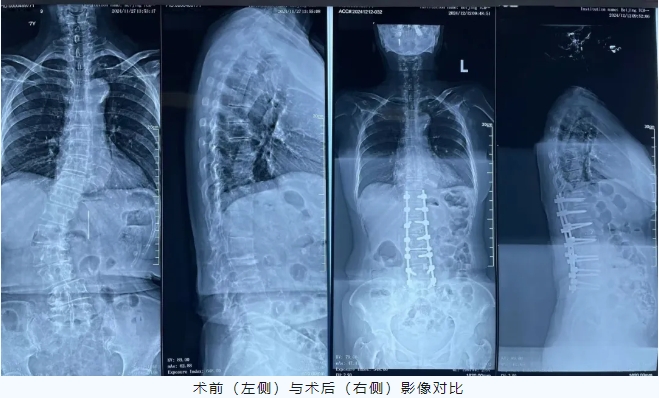

宽街·妙手 | 77岁老人“长高”4厘米,腰不痛、腿不软了……一场手术扶正侧弯脊柱,这种病老年人很常见

发布时间:2024-12-23 作者:骨伤科

77岁,经过一场手术,“长高”了4cm,腰不痛了,腿也不软了。这是怎么回事?近日,齐奶奶在首都医科大学附属北京中医医院骨伤科接受了脊柱侧弯矫形手术,让她可以摆脱了轮椅,恢复了正常人生活,而且“长高”了4cm。

齐奶奶十几年前就开始出现腰痛,随着年龄的增长,腰痛慢慢加重、脊柱逐渐出现歪斜、双腿无力。近年来,病情愈发严重,连站立行走等日常生活都很难进行。齐奶奶和家人辗转北京多家大型三甲医院就诊,但却因年龄大、侧弯矫形手术创伤大等原因,医生均建议她保守治疗。难道晚年就要在轮椅上度过了?为了更高的生活质量,齐奶奶仍想为自己争取治疗机会。在家人推荐下,抱着满腔信任和一丝希望的她慕名来到了北京中医医院骨伤科韦竑宇主任医师门诊就诊。韦竑宇认真查看了既往的检查结果和齐奶奶的情况。一句“可以手术!”的答复仿佛一颗定心丸,驱散了齐奶奶和家属心头的阴霾。入院后,骨伤科医疗团队为齐奶奶进行了全面检查,在放射科支持下,进一步为齐奶奶完善脊柱全长片测量,脊柱侧弯Cobb角高达42°。由于成人侧弯脊柱僵硬,必须做到每个节段都进行减压松解才能实现矫形,创伤较大,不利高龄患者术后恢复。

为此,韦竑宇带领尹辛成、董春科、张翔、肖辉灯主诊团队术前完善了详细的手术方案,制定患者矫形节段(T11-L5)。由于齐奶奶年龄大且存在多种并发症,麻醉风险较高,麻醉科制定了详细的麻醉方案为手术保驾护航。术中医疗团队采用超声骨刀进行椎板切除减压,并且采用创伤更小的多节段TLIF截骨矫形术。在团队密切配合下,手术取得圆满成功。

术后在护理团队的精心呵护下,齐奶奶恢复良好,腰不痛了、脊柱变直了、个子“长高”了4cm,终于又可以抬头挺胸往前走了。